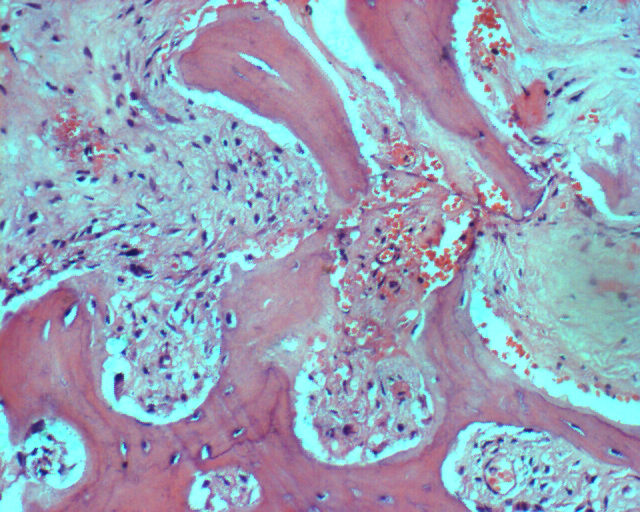

图 25 组织学特点:纤维性间质,产生胶元的梭形细胞交织排列,数量不等的骨样基质,成骨细胞有一定异型,肿瘤形成较多层状骨。